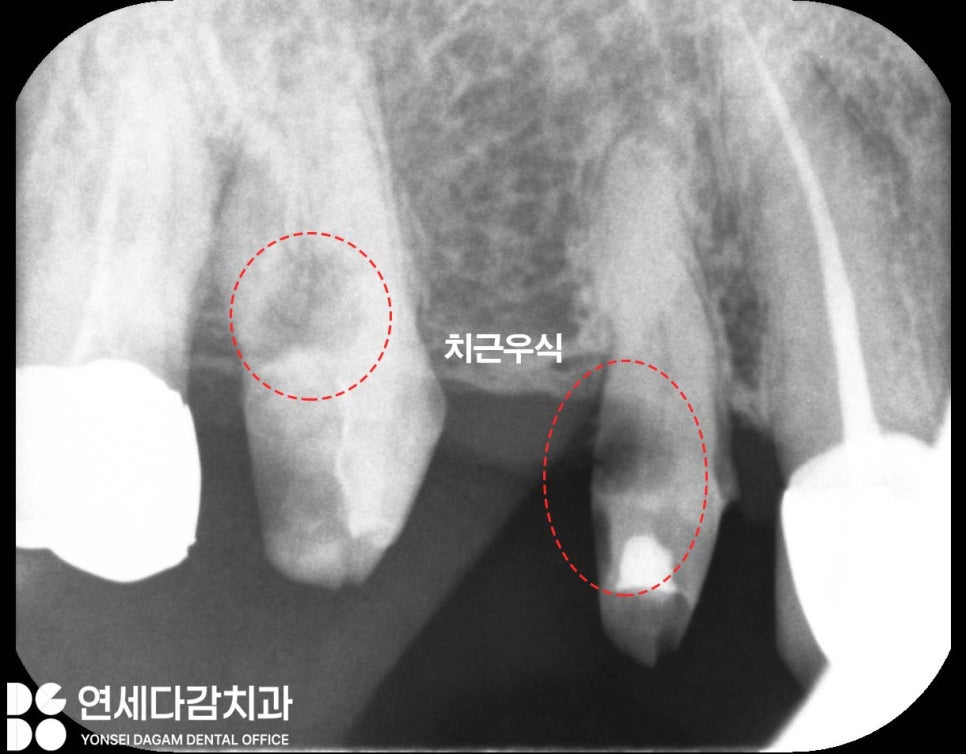

치근 우식이란

잇몸 아래 치아 뿌리 부위에

생기는 충치를 말합니다.

치근 우식이 관찰되면

보철 전체를 제거하고 정확한 치아 상태를

재평가하는 과정이 필요합니다.

치근 우식이 심한 경우에는

발치가 불가피하게 됩니다.